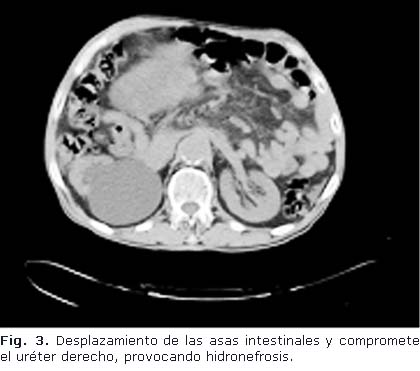

Tomografía Axial Computadorizada con contraste vía oral y endovenosa: Se aprecia gran masa tumoral compleja, que se extiende desde la excavación pélvica, donde comprime el recto hacia la derecha y la vejiga hacia delante (Fig. 2 y 3), desplaza las asas intestinales y compromete el uréter derecho, provocando hidronefrosis. El tumor mide aproximadamente 28 x 29 cm. Aorta ateromatosa, no lesión focal en hemiabdomen superior. No líquido libre en cavidad. La próstata no se logra identificar.